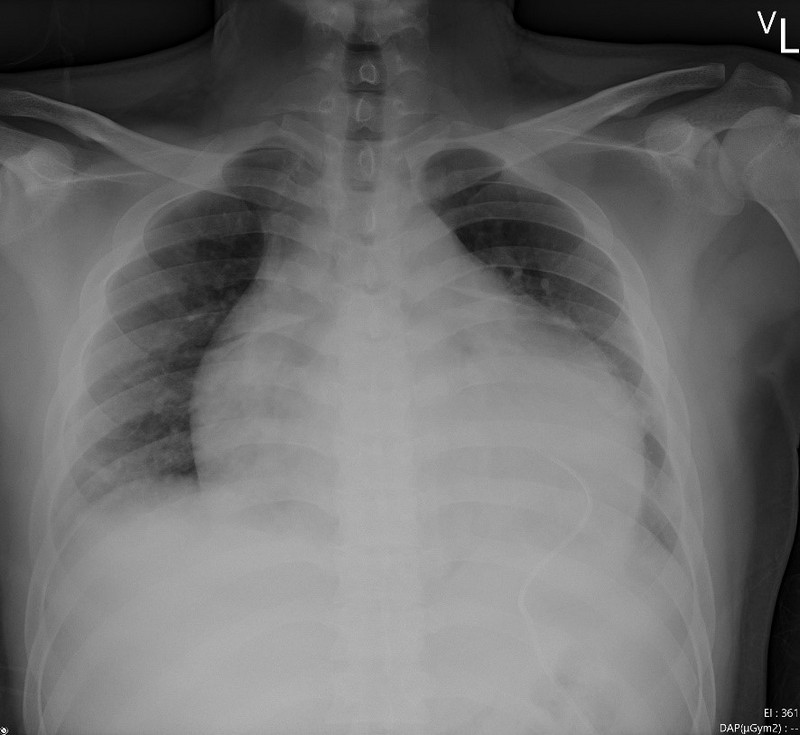

經X光檢查,兩人均有心臟擴大、肺水腫,心電圖檢查ST段上升、心律不整;大部分病人出現ST段上升,是特定血管急性心肌梗塞,王惠生醫師說,但這兩位病人都是瀰漫的心電圖異常變化,無法以特定血管阻塞解釋,但合併休克,擔心快速惡化會有生命危險,診視後隨即收住院,在內科加護病房觀察及探查原因,並用利尿劑、消炎藥物治療;所幸發現得早並即時投藥進行支持式療法,病情在三天後即逐漸改善,並轉出加護病房。目前,兩人均已痊癒出院。

圖:胸部X光可見心臟嚴重擴大,放置引流管減少積水,並以支持式療法治療,數日後才逐漸改善,最後病患順利出院。(王惠生提供)